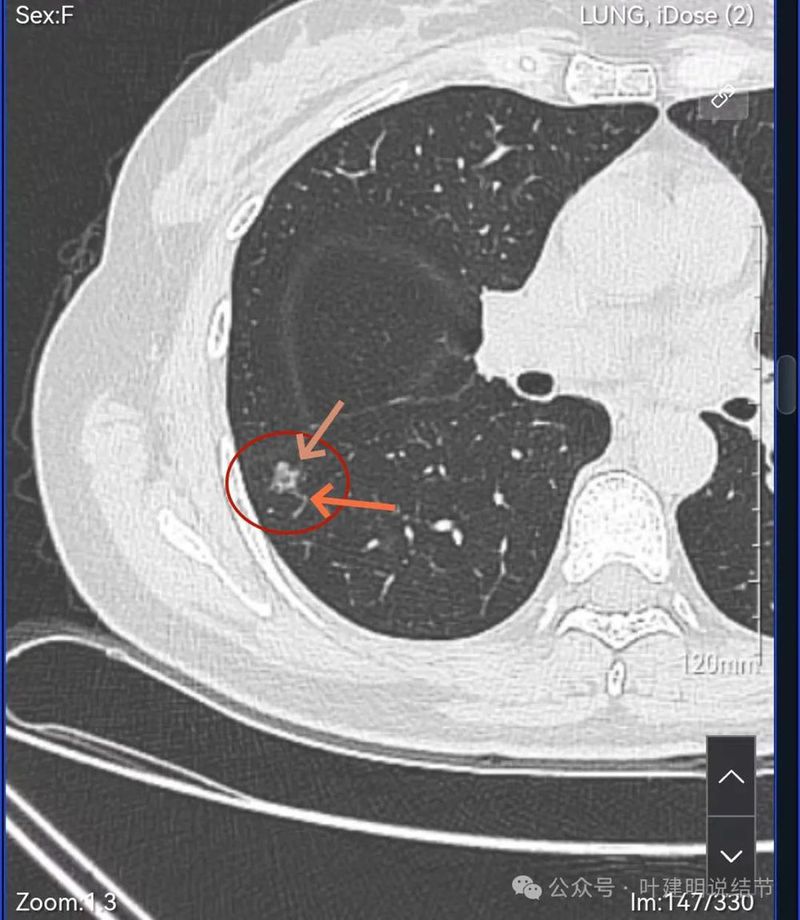

密度不太纯,轮廓与边界清。

表面分叶,中间空泡,边缘有磨玻璃成分,叶间胸膜凹陷。